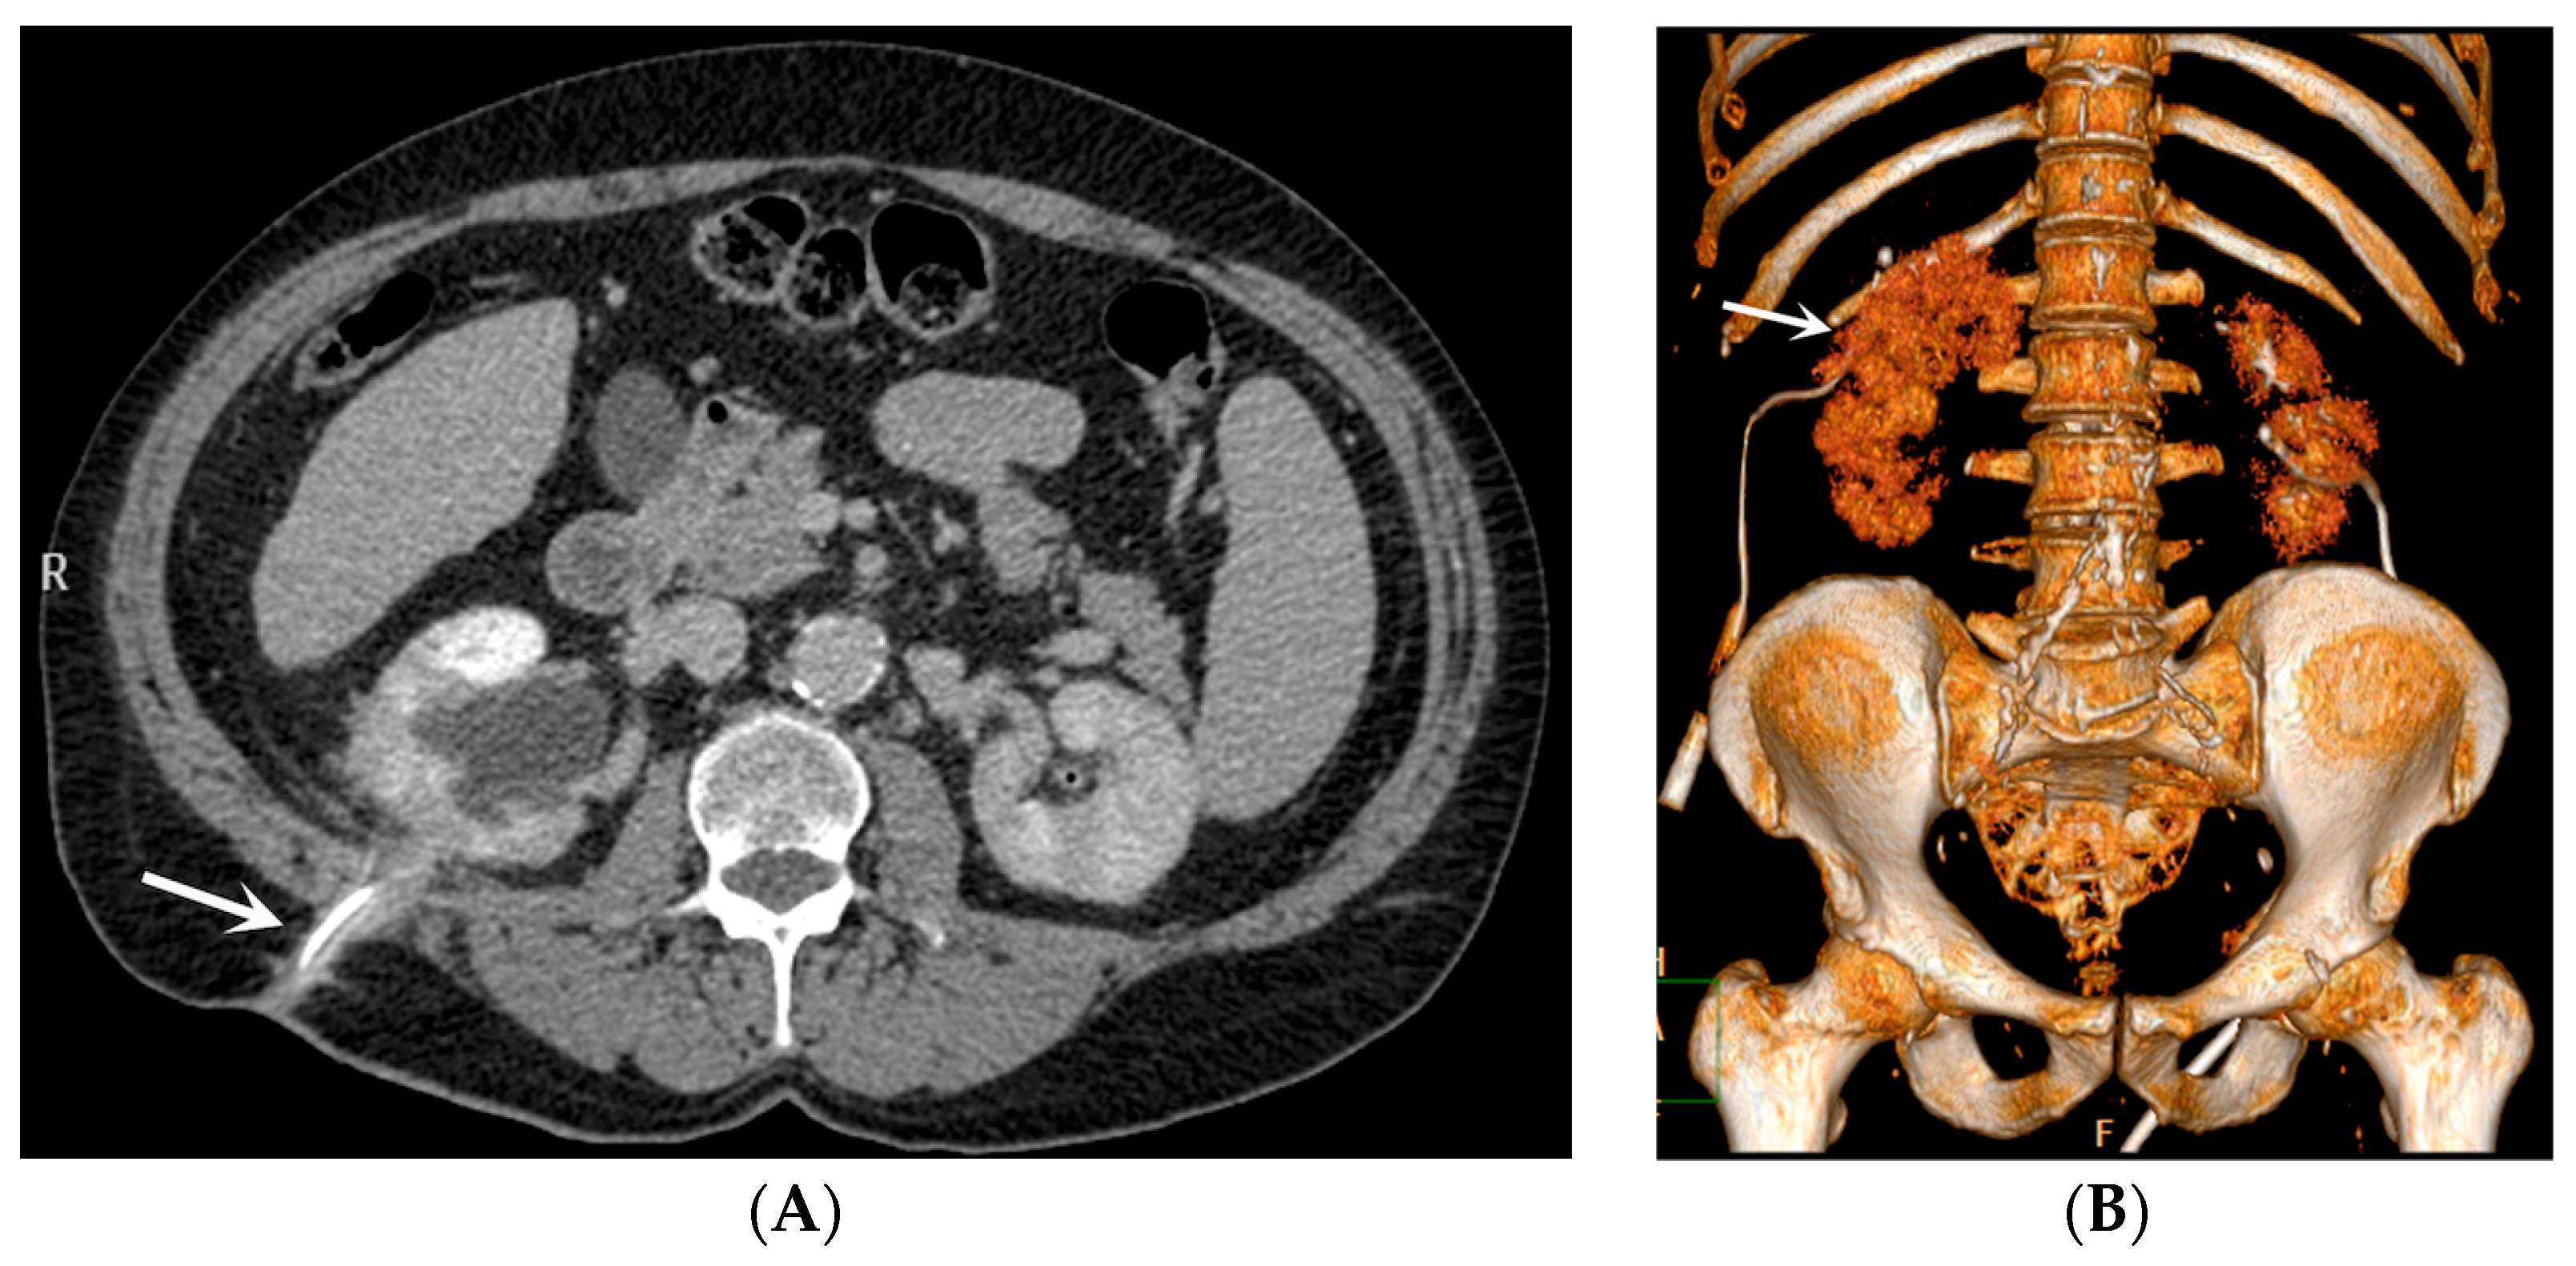

- Urine leakage: Stents crafted from more rigid materials have the potential to perforate the ureter, collecting system, and kidney parenchyma during placement, leading to the formation of fluid collections or urine leakage, often resulting in a urinoma [35] (Figure 9). A urinoma is a collection of extravasated urine outside of the urinary tract. The optimal diagnostic imaging studies for this condition include contrast material-enhanced CT with delayed imaging (10–20 min), CT–cystography, and a retrograde urethrography [36,37]. In a CT scan, a urinoma may manifest as a restricted or unrestrained collection within the intra- or retro-peritoneal compartment, with the latter occurrence being more prevalent. Its attenuation values can vary from 0 to 20 HUs before the administration of intravenous contrast, subsequently intensifying up to 200 HUs after contrast administration (Figure 9). The irritation from the urine may lead to the formation of a fibrous capsule surrounding the urinoma, which can occasionally become calcified. Not infrequently, a dystrophic calcification of the urinoma may occur, which results from an inflammatory and fibrotic reaction to the extravasated urine [38]. Urinomas, typically small initially, are often resolved on their own without intervention. However, in cases of significant injury or a larger urinoma failing to reabsorb, urological or interventional radiological procedures may be necessary. Neglecting intervention can lead to complications, such as abscess, electrolyte imbalance, hydronephrosis, and urosepsis [37,38].